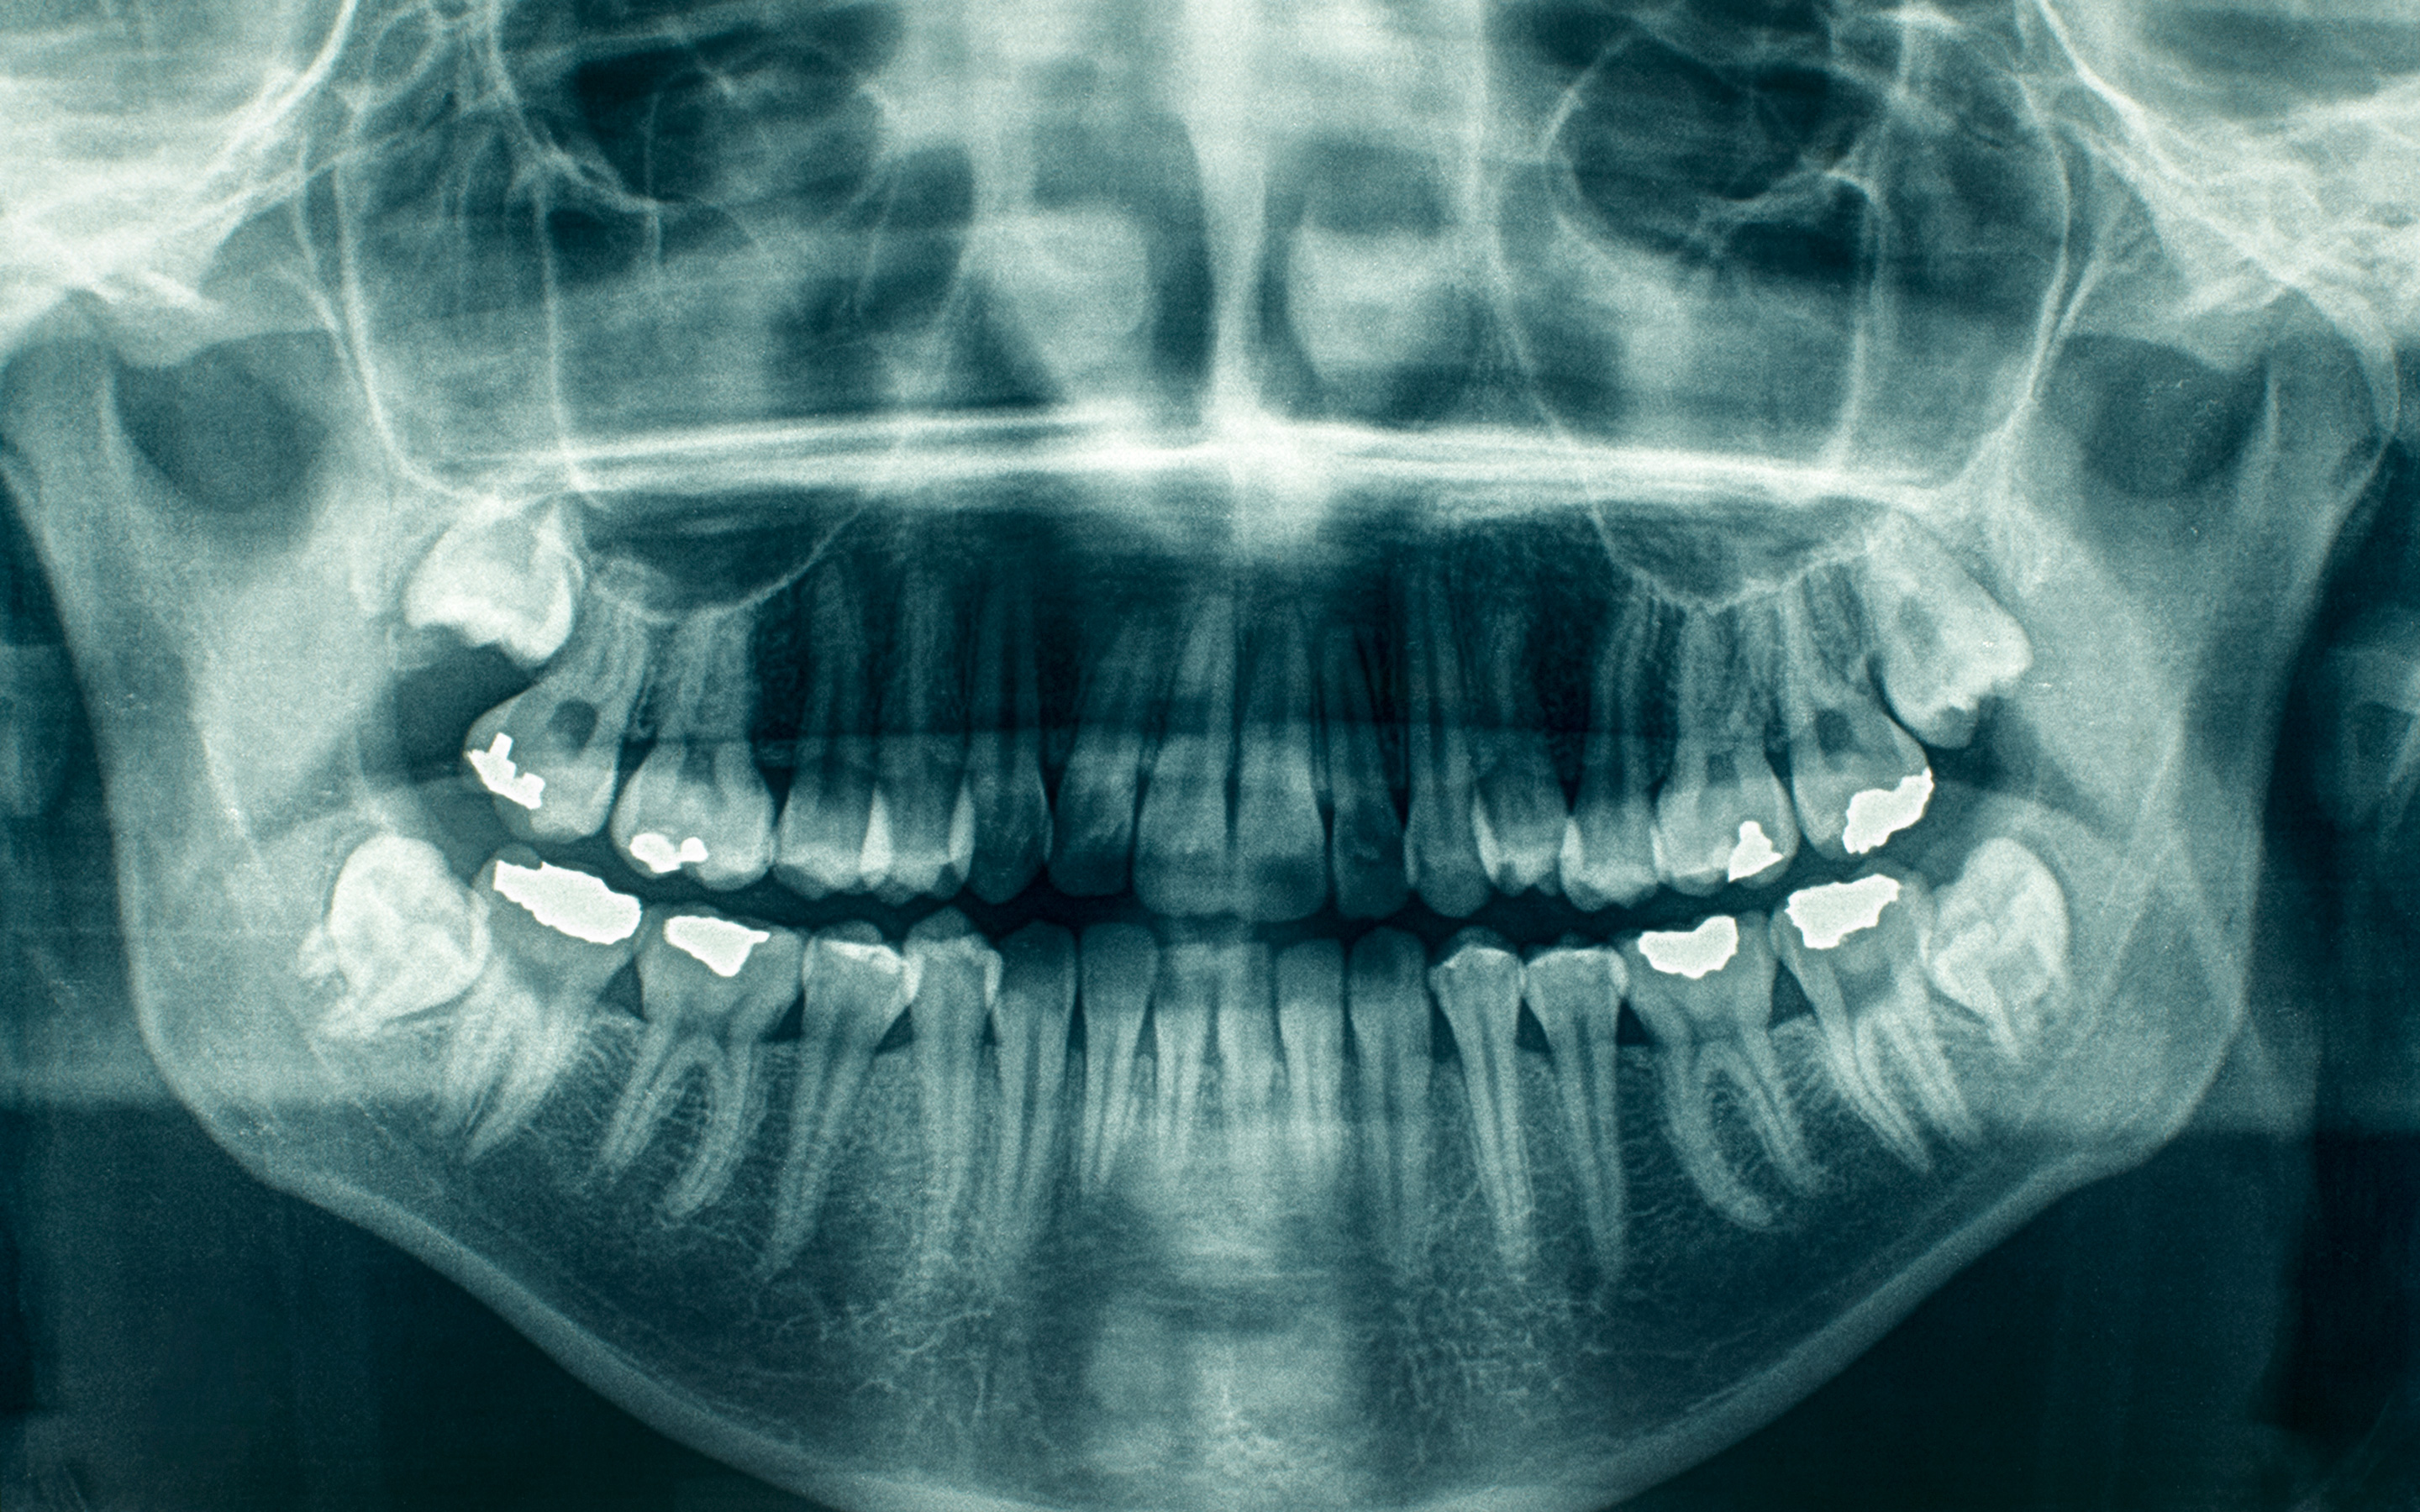

Digital dental x-rays or dental radiographs are a useful diagnostic tool when helping your detect damage and disease not visible during a regular dental exam. How often X-rays should be taken depends on your present oral health, your age, your risk for disease, and any signs and symptoms of oral disease. For example, children may require X-rays more often than adults because their teeth and jaws are still developing and their teeth are more likely to be affected by tooth decay than those of adults. At CyprusDental, we will review your history, examine your mouth and then decide whether or not you need X-rays.

CyprusDental uses the latest technology of digital x-ray/radiography. This new method, which is not yet widely used in dental offices involves a small electronic sensor unit (instead of the tradiotional x-ray film) sending pictures to a computer to be recorded and saved. These image can be viewed on a computer screen. Research shows that less radiation is needed to make an image with digital radiography than with standard dental X-rays.

Digital dental X-rays are done to:

Find problems in the mouth such as tooth decay, damage to the bones supporting the teeth, and dental injuries (such as broken tooth roots). Dental X-rays are often done to find these problems early, before any symptoms are present.

Find teeth that are not in the right place or do not break through the gum properly. Teeth that are too crowded to break through the gums are called impacted.

Find cysts, solid growths (tumors), or abscesses.

Check for the location of permanent teeth growing in the jaw in children who still have their primary (or baby) teeth.

Plan treatment for large or extensive cavities, root canal surgery, placement of dental implants, and difficult tooth removals.

Plan treatment of teeth that are not lined up straight (orthodontic treatment).